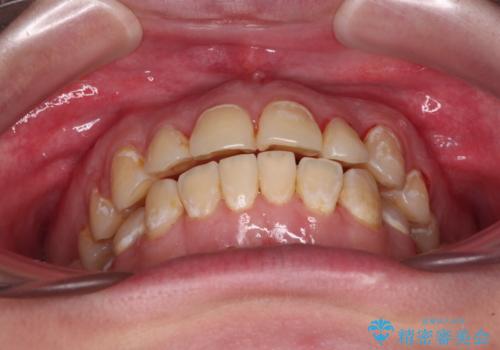

- 前歯のデコボコとクロスバイトが気になり、インビザラインによる矯正治療を希望して来院された患者様です。

上顎側切歯(上の真ん中から2番目の歯)が舌側転位している場合、無理して動かそうとすると歯髄壊死を起こすリスクが高い印象があります。

インビザライン単体でも治療は可能ですが、安全策としてインビザラインで歯列を移動する前に上顎前歯をワイヤー矯正で整え、その後上下歯列をインビザラインにて矯正治療を行うこととしました。

舌側転位している側切歯特有の、切縁の位置が不揃いであったり、根元が内側に引っ込んだ状態であったりという、インビザライン独特の仕上がりになることなく、きれいに整った歯列とすることができました。